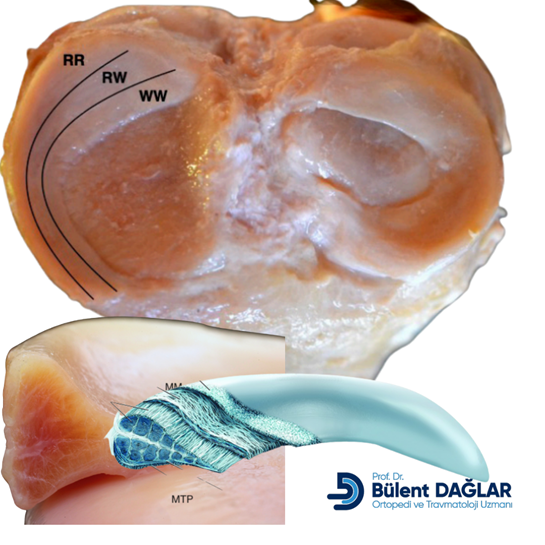

Menisküs Yırtığı:

- Menisküs: Diz ekleminde yastık görevi gören, C şeklindeki kıkırdak dokulardır.

- Belirtiler: Ani bir hareket (merdiven inme, çömelme ve çömelme pozisyonundan kalkma gibi) sırasında keskin ağrı ile başlayabilir. Şişlik, ağrı (özellikle dizin iç veya dış tarafında), dizde kilitlenme hissi veya tam açamama gibi durumlar olabilir. Orta yaş civarında, yaşa bağlı dejenerasyon (yıpranma) nedeniyle basit bir zorlanmayla da yırtık oluşabilir.

Diz Kireçlenmesi (Osteoartrit):

- Açıklama: Eklem kıkırdağının zamanla aşınmasıdır.

- Belirtiler: Genellikle orta yaş ve üzeri kişilerde görülür. Ağrı, merdiven inip çıkarken, uzun süre oturduktan sonra kalkarken artabilir. Dizde sertlik ve şişlik görülebilir. İç taraftaki ağrı, dizin iç kısmındaki eklem yüzeyinin kireçlenmesine bağlı olabilir.